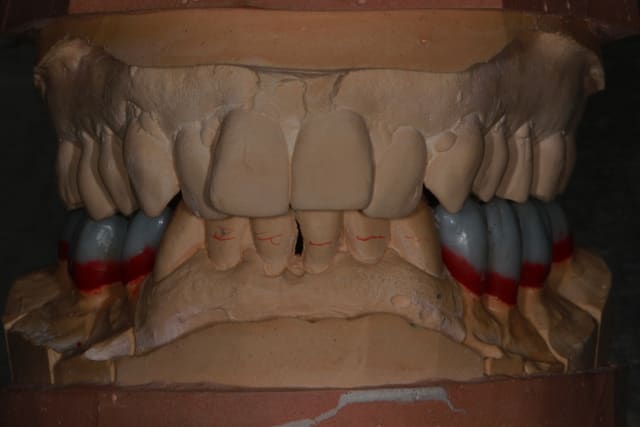

Wax up et taille crayon...

Empreinte, détourage et préparation des cires avec une occlusion différente de celle du wax up, un peu plus de DV

Le trait rouge sur les incisive donne à peu de chose prêt l'origine...